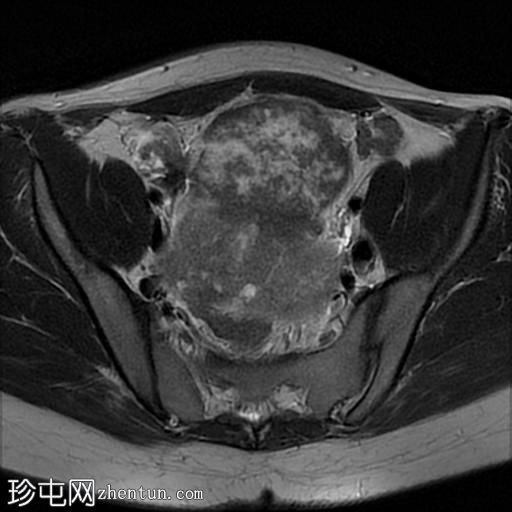

轴位

T2加权像

盆腔内可见多个边界清晰的肿块:

其中一个位于子宫上方,T2加权像呈中等信号,中心区域呈高信号,增强T1脂肪抑制像未见强化。右侧卵巢增大,增厚的血管蒂扭曲,未见强化,轴位和矢状位T2加权像均显示清晰。

另一个位于子宫后窝,T2加权像呈中等信号,增强扫描显示明显强化。

轻度腹腔积液